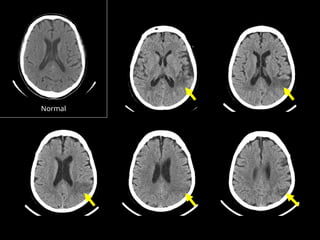

Chronic Infarct Chronic Infarct Ensuite, recherchez les signes d’infarctus Ensuite, recherchez les signes d’infarctus chronique chronique: : Deplacement modéré de la ligne médiane due à l’atrophie Retraction du parenchymes de la voute due à l’atrophie Zone Focale d’hypodensité